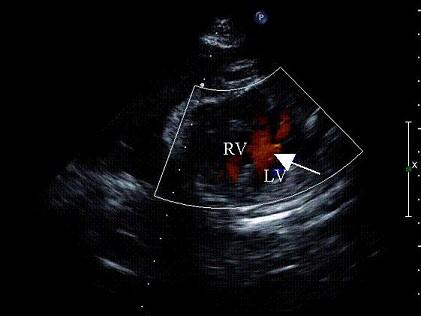

孕8周时感冒,产前超声检查胎儿心脏见图,最可能的诊断是 ( )A、大动脉转位B、正常心脏C、房间隔缺损D、室间隔缺损E、单心室

选项 A、大动脉转位 B、正常心脏 C、房间隔缺损 D、室间隔缺损 E、单心室

答案 D